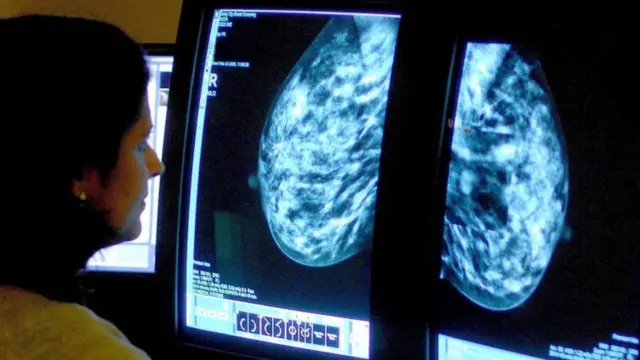

چھاتی کا سرطان: کیا 50 کے بجائے 40 برس کی عمر میں سکریننگ ٹیسٹ زیادہ خواتین کی جانیں بچا سکتا ہے؟

برطانیہ میں ایک تحقیق کے مطابق اگر خواتین میں 50 کے بجائے 40 برس کی عمر سے ہی چھاتی کے سرطان کے ٹیسٹ شروع کر دیے جائیں تو زیادہ جانوں کو بچایا جا سکتا ہے۔

برطانیہ میں 50 سے 70 برس کی خواتین کا ہر تین سال میں ایک مرتبہ چھاتی کے سرطان کا ٹیسٹ کیا جاتا ہے۔

50 سال سے کم عمر خواتین کو یہ مفت سہولت میسر نہیں ہے کیونکہ عموماً ان میں چھاتی کے سرطان ہونے کی شرح قدرے کم ہوتی ہے اور ان کی چھاتی کا ٹشو سخت تر ہوتا ہے جس کی وجہ سے اس ٹیسٹ کے نتائج کو معلوم کرنا قدرے مشکل ہوتا ہے۔